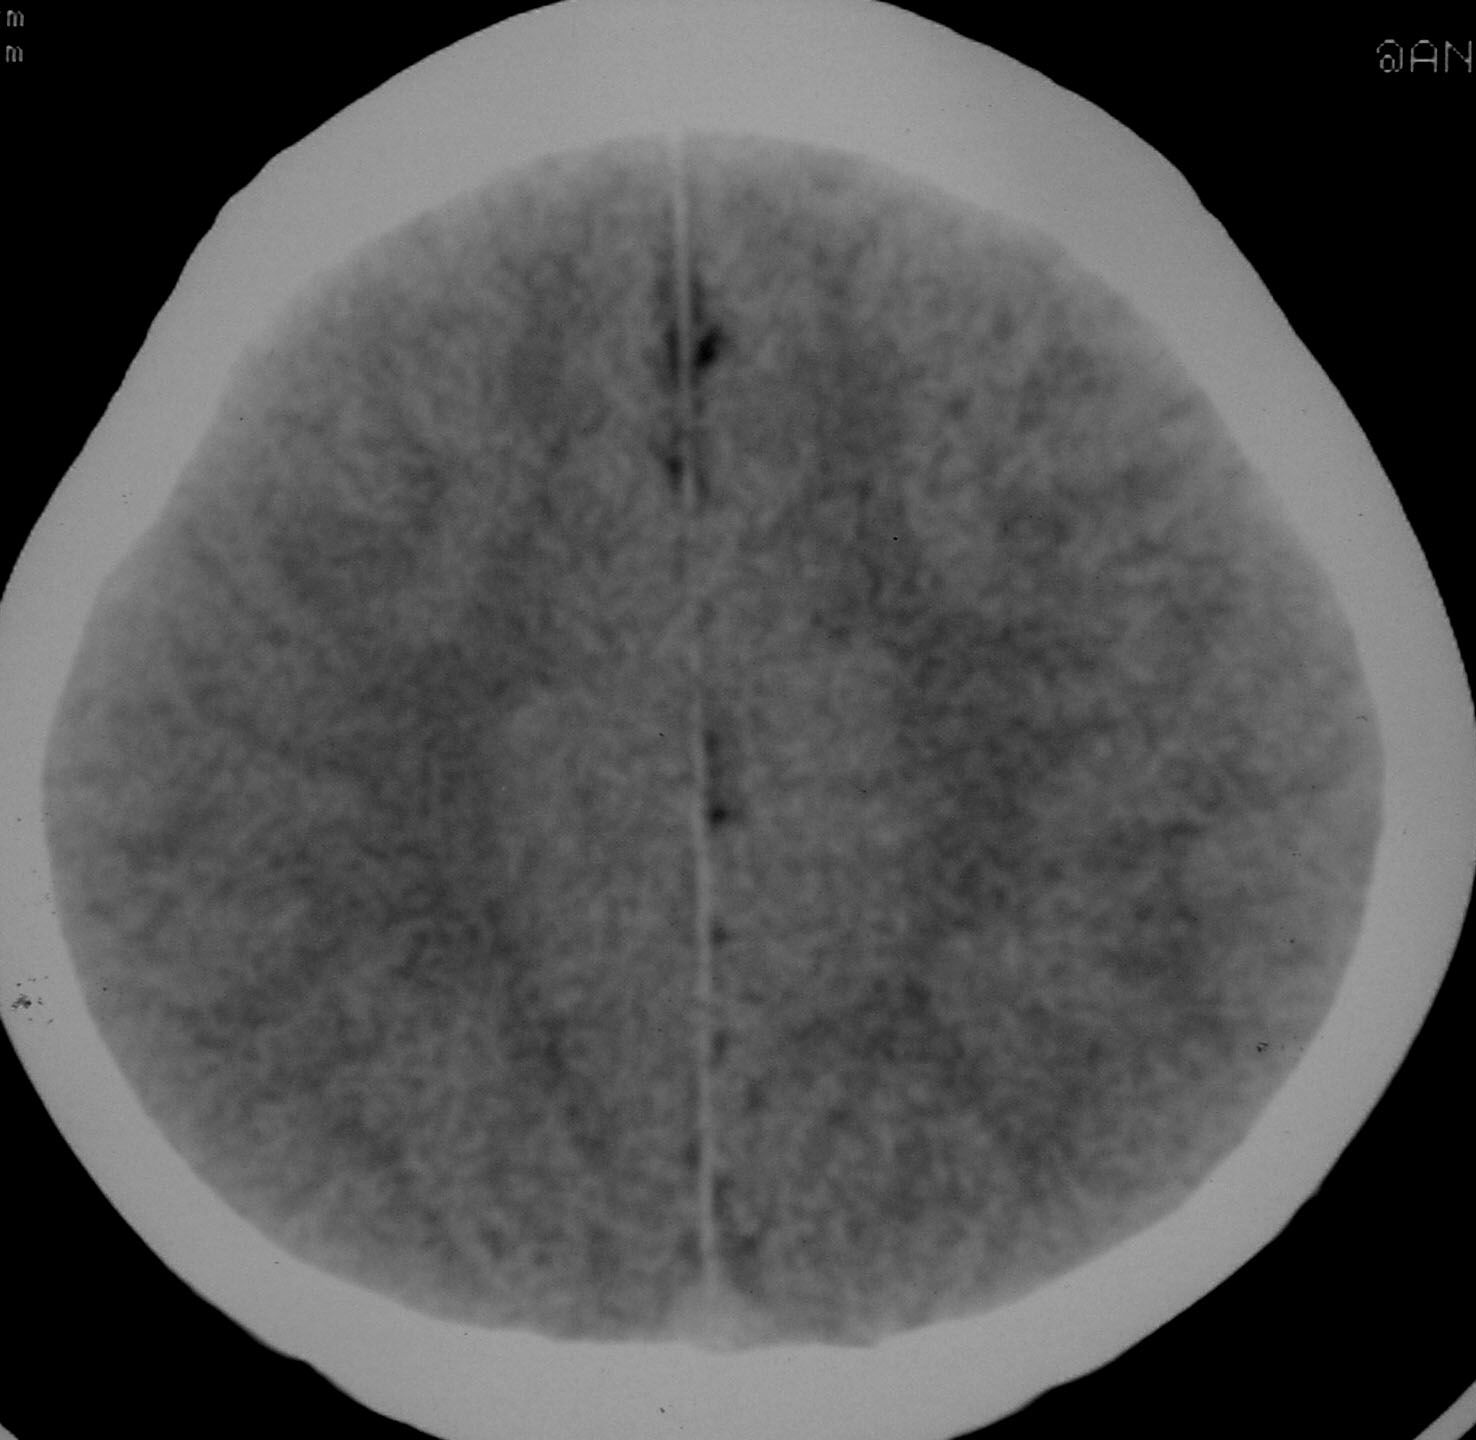

以下是引用余辉在2007-4-28 19:55:00的发言:[br]血管畸形?增强一下

以下是引用jw-830在2007-4-28 20:22:00的发言:[br]考虑血管畸形可能建议增强

以下是引用ysxyy在2007-4-29 21:14:00的发言:[br]像是假像,如果不放心可以偿试一下:[br]你用听眦线为基线扫一下,再用听眶线扫一下,就是说用不同的角度扫同一个地方;[br]看看有无变化,是不是有相同或相似的表现,即可鉴别;